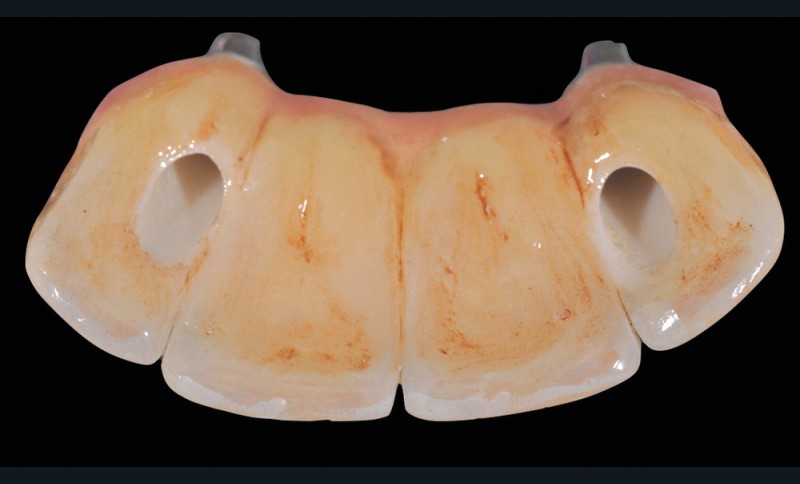

La méthode la plus efficace est probablement le pré-scellement de la suprastructure sur un duplicata du pilier. Ce dernier peut être livré par le laboratoire en même temps que les pièces prothétiques, réalisé alors le plus souvent en résine.

Une autre méthode, réalisable au cabinet, consiste à utiliser du silicone light en pistolet pour remplir l’intrados et, après la prise, désinsérer pour obtenir un duplicata rapide et économique (fig. 3).